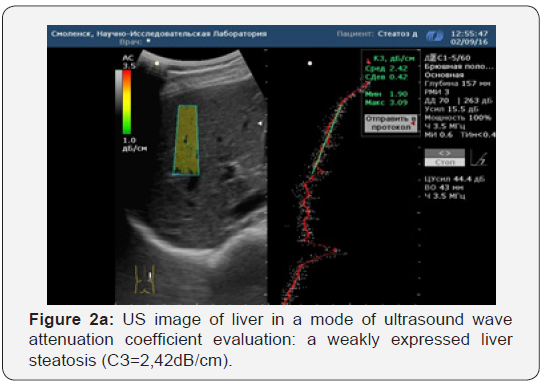

Various stages of NAFLD were identified in the histological study of liver biopsy materials. Evaluation of the results was carried out according to the SAF scale for semi-quantitative evaluation of gravity and the stage of NAFLD. We evaluated the correlation of the histological evaluation of liver biopsy samples with the ultrasound wave attenuation coefficient (Figure 2a, 2b & Figure 3a, 3b). All patients in the clinical group who underwent liver biopsy under the ultrasound were divided into groups, depending on the severity of fat changes in hepatocytes according to the SAF scale. Thus, by performing an analysis of the comparison of histological specimens of liver biopsy samples and ultrasound data of the quantitative evaluation of the ultrasound wave attenuation in dB/cm, it can be concluded that the correlation between liver biopsy and ultrasound wave attenuation coefficient evaluation is sufficient for in-formativeness at the initial and significant stages of liver steatosis (S0 r=0.86; S3 r=0.84). In stages S1 and S2, the informativity is lower, and it requires the introduction of more patients in the study protocols, carrying out liver elastography and increasing the number of liver biopsies in clinical groups.